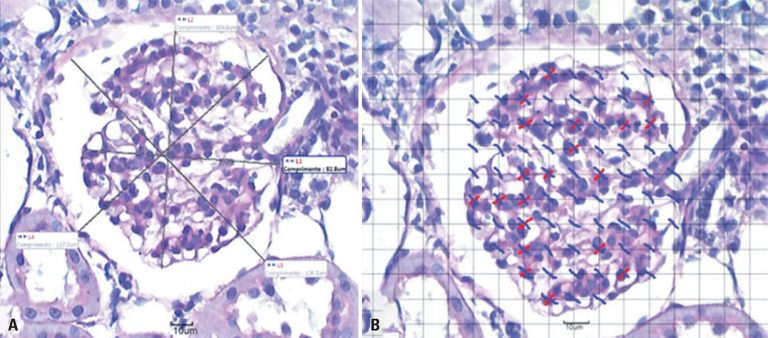

RESUMO Objetivo Analisar se a inalação passiva da fumaça do cigarro proporciona alterações morfológicas, estruturais e funcionais nos rins de ratos. Métodos Ratos Wistar, com oito semanas de idade, pesando, em média, 260g, foram divididos em Grupo Controle e Grupo Tabagista. Cada grupo foi subdividido em quatro grupos de dez animais para análise morfofuncional, em um período de sete e 28 dias. O Grupo Tabagista foi exposto à fumaça de 40 cigarros por dia, em horários determinados e equipamento automatizado […]